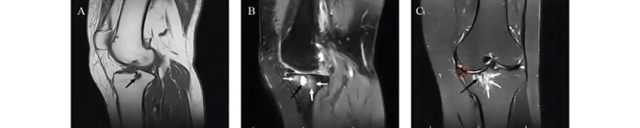

骨关节炎进展中,软骨下骨经历了一系列的特征性病理变化。首先是早期微损伤:机械应力异常导致骨重建失衡,成骨细胞与破骨细胞无法协同工作。破骨细胞过度活化会使骨板变薄、孔隙率增加,骨小梁密度降低、结构破坏,出现微骨折,此阶段在磁共振成像(MRI)上可观察到软骨下骨微骨折的低信号表现(图1)。此阶段软骨形态学改变尚不明显,但软骨基质中蛋白聚糖减少,炎症因子和基质金属蛋白酶水平已显著升高。微损伤进一步发展为骨髓水肿样病变(SBMLs),表现为骨髓纤维化、血管异常和局部脂肪坏死,是骨关节炎进展的重要影像学标志,在磁共振T2加权脂肪抑制序列中呈现高信号区域(图2)。骨髓水肿样病变通过增加骨-软骨间物质交换通道,促进炎症因子和破骨细胞前体侵入软骨,加速软骨降解,并与骨关节炎疼痛密切相关。长期异常力学刺激下,骨髓水肿区域逐渐形成软骨下囊肿(SBCs),其内含血管、神经纤维和炎症因子,在磁共振T1加权像中表现为低信号囊性结构,周围伴骨髓水肿(图3)。晚期则出现软骨下骨硬化,骨小梁增厚、排列紊乱,导致关节应力分布异常,加剧软骨损伤。

图3 67岁女性膝关节骨关节炎的磁共振成像。(A)矢状位T1加权像显示胫骨近端低信号软骨下骨囊肿(黑色箭头)。(B)矢状位脂肪抑制质子密度(PD)MRI显示胫骨近端软骨下骨囊肿(黑色箭头),周围伴弥漫性骨髓水肿(白色箭头)。(C)冠状位T2加权中间加权脂肪抑制像显示胫骨近端软骨下骨囊肿,内部信号强度不均(黑色箭头),周围伴弥漫性骨髓水肿;关节内侧红色圆圈示骨赘形成